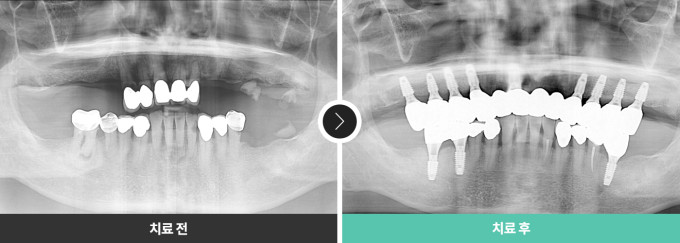

전후 사진

의료법에 의거하여 전후 사진은 로그인 후 확인이 가능합니다.